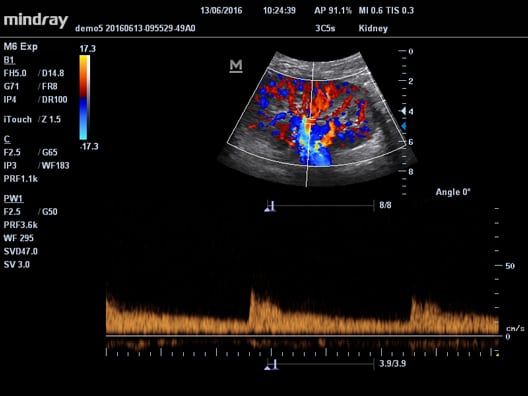

- Pulsní, Spektrální Doppler (PW), citlivý Barevný Doppler (CFM), ultracitlivý směrový Power Doppler (PDI), anatomický - M mód a Stress Echo

- triplexní mód a automatické poměření celého spektra Pulsního Doppleru

- 2 živé obrazy B/CFM (Dual live B/CFM mód)

- Power 3D – (4D zobrazení cév v CFM módu)